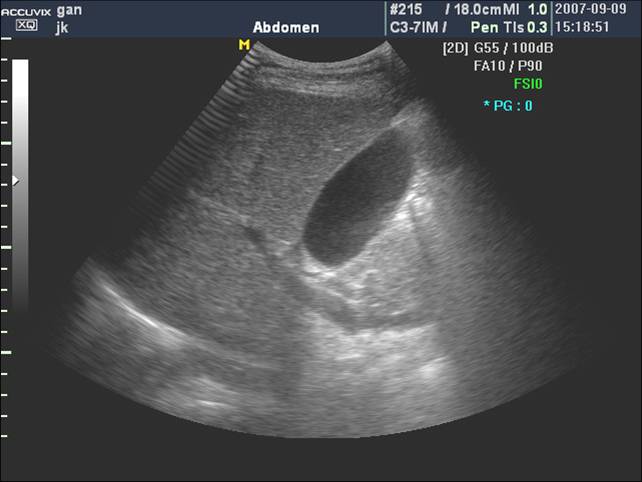

(二)通过肝静脉进行分叶

肝静脉主干在叶间裂或段间裂内行走,易于超声显示,最便于进行肝脏分叶、分段。

1. 肝右静脉行走于右叶间裂内-右前、后叶分界

2. 肝中静脉行走于正中裂的后半部和尾状叶内,右半肝与左半肝分界

3. 肝左静脉近端走行左叶间裂内-左内外叶分界

4. 肝左静脉远端位于左段间裂内-为左外叶上段和下段分界

肝左右叶的超声分界标志(肝中静脉)

肝左右叶的超声分界标志(胆囊切迹-下腔静脉左缘连线)

肝左内外叶的超声分界(肝圆韧带-门静脉左支矢状部-静脉韧带)

肝左外叶上下段的超声分界

肝右叶上下段的超声分界